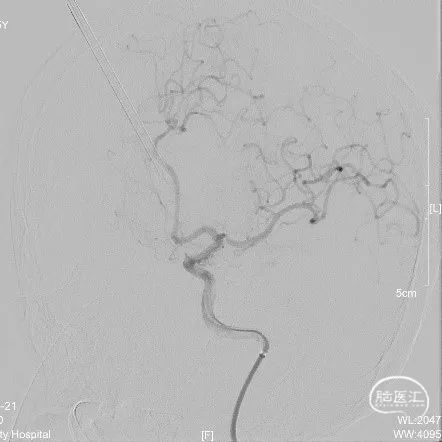

术毕即刻造影见该动脉瘤被完全栓塞,未见残留。

拟术后三月复查颅脑MRA;术后半年复查DSA。